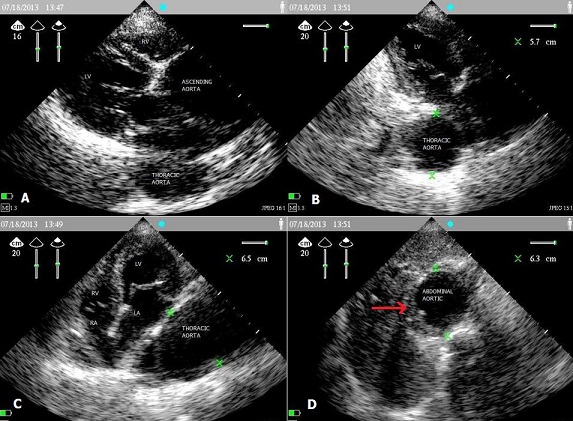

Aneurysm of the thoracic and abdominal aorta in a patient aged 67 years detected incidentally in pre-anesthesia consultation

An aneurysm is a localized irreversible dilatation of the aortic wall resulting from an alteration of elastic fibers in the media. The main risk is rupture. It depends on the size and growth rate. Abdominal ultrasound has become the easiest and most reproducible for screening, only the anteroposterior and transverse diameters must be selected. We report the case of patient a 67 years old, saw pre-anesthesia consultation revealed fortuitously an aneurysm of the ascending aorta of 7.5 cm diameter, 5.7 cm of the descending thoracic aorta, and 6.3 cm of the abdominal aorta below the renal arteries associated with thrombus.the patient is referred by treatment to the cardiovascular consultation, to discuss the treatment of aneurysm first before any surgery.